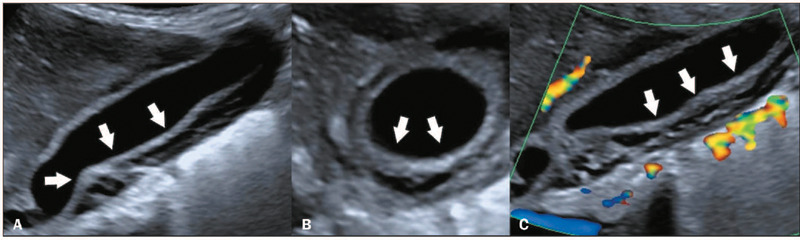

The dengue virus, a member of the family Flaviviridae, is transmitted by Aedes mosquitoes and causes a viral disease known as dengue fever that is prevalent in tropical and subtropical regions. It is estimated that there are 100-400 million new infections every year, with underreporting due to limited surveillance systems. The presentation ranges from asymptomatic to dengue shock syndrome. Brazil is now facing an endemic of dengue, having seen a significant seasonal increase of over 4.5 million in the number of probable cases reported. Imaging exams such as ultrasound, computed tomography, and magnetic resonance imaging are crucial for detecting complications of dengue, aiding in the clinical management and differential diagnosis, especially in severe cases. The aim of this study was to illustrate the radiological findings of dengue, focusing on emergency and critical care settings.